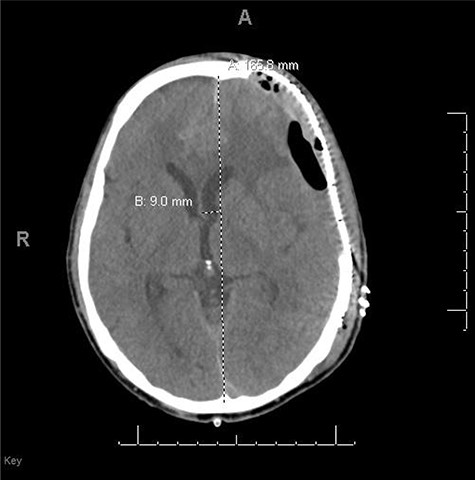

He had a significant recovery, to the point where he was awake with mild right paresis. He was following commands briskly but remained nonverbal. On hospital day 26, he developed neurological deterioration with decreased mental status and worsening right hemiparesis. Clinical examination noted pronounced new indentation of his hemicraniectomy flap site. CT head showed a rightward shift away from the craniectomy site and impending herniation (Fig. 4).

CT head POD26 from craniectomy demonstrating findings consistent with SSFS.